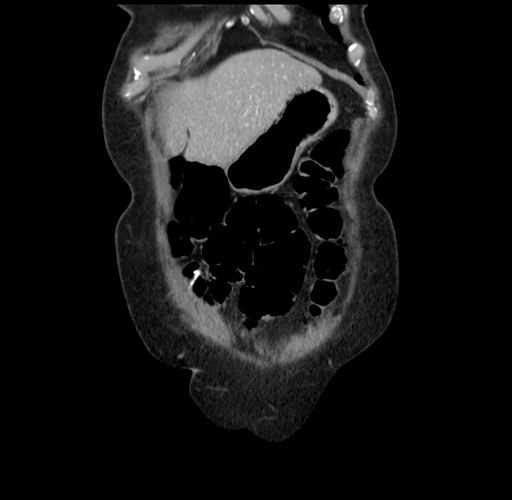

Pre-Chemo: Coronal Venous